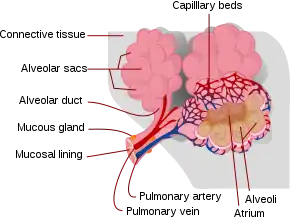

It is usually caused by blunt trauma to the chest.[1] Other causes include the shock wave from an explosion or penetrating injury.[1] The underlying mechanism involves injury to the lung parenchyma, leading to leakage of fluid from the capillaries into the alveoli.[1] Diagnosis is by medical imaging such as chest X-ray, CT scan, or ultrasound.[1] Associated injuries may include rib fractures or a pneumothorax.[2]

Bleeding and swelling

In contusions, torn capillaries leak fluid into the tissues around them.[32] The membrane between alveoli and capillaries is torn; damage to this capillary–alveolar membrane and small blood vessels causes blood and fluids to leak into the alveoli and the interstitial space (the space surrounding cells) of the lung.[9] With more severe trauma, there is a greater amount of edema, bleeding, and tearing of the alveoli.[16] Pulmonary contusion is characterized by microhemorrhages (tiny bleeds) that occur when the alveoli are traumatically separated from airway structures and blood vessels.[23] Blood initially collects in the interstitial space, and then edema occurs by an hour or two after injury.[29] An area of bleeding in the contused lung is commonly surrounded by an area of edema.[23] In normal gas exchange, carbon dioxide diffuses across the endothelium of the capillaries, the interstitial space, and across the alveolar epithelium; oxygen diffuses in the other direction. Fluid accumulation interferes with gas exchange,[33] and can cause the alveoli to fill with proteins and collapse due to edema and bleeding.[23] The larger the area of the injury, the more severe respiratory compromise will be.[16]